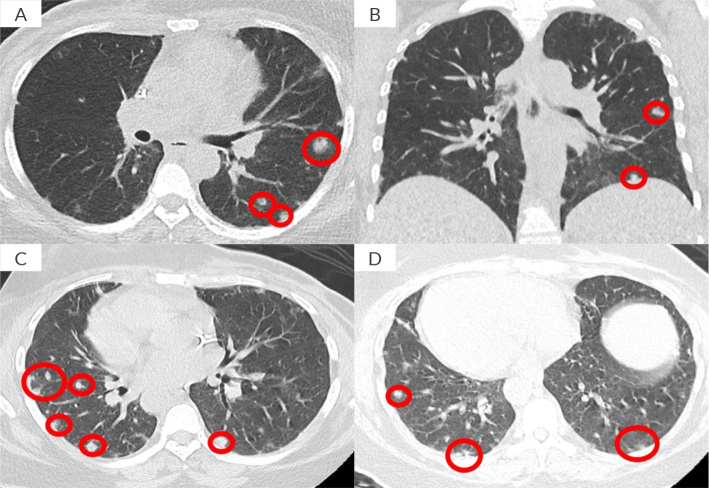

Case report: We report the case of a 46-year-old female with metastatic HER2-mutated breast cancer who had received multiple lines of HER2-targeted therapies. The patient presented with suspected lung and mediastinal lymph node progression, despite a good response at other affected sites. A lymph node biopsy revealed non-necrotizing pulmonary granulomas, with negative microbiological testing. Further evaluations showed highly elevated anti-PR3 autoantibodies, while angiotensin-converting enzyme (ACE) and calcium levels remained within the normal range. Pulmonary function tests confirmed a restrictive syndrome. Nasal fibroscopy identified chronic sinusitis with massive nasal polyposis, without renal or cutaneous involvement. High-dose corticosteroid therapy was initiated, leading to a favourable response. Based on the clinical presentation, radiological findings, and pathological features, we concluded that the granulomatosis was related to HER2-targeted therapy.